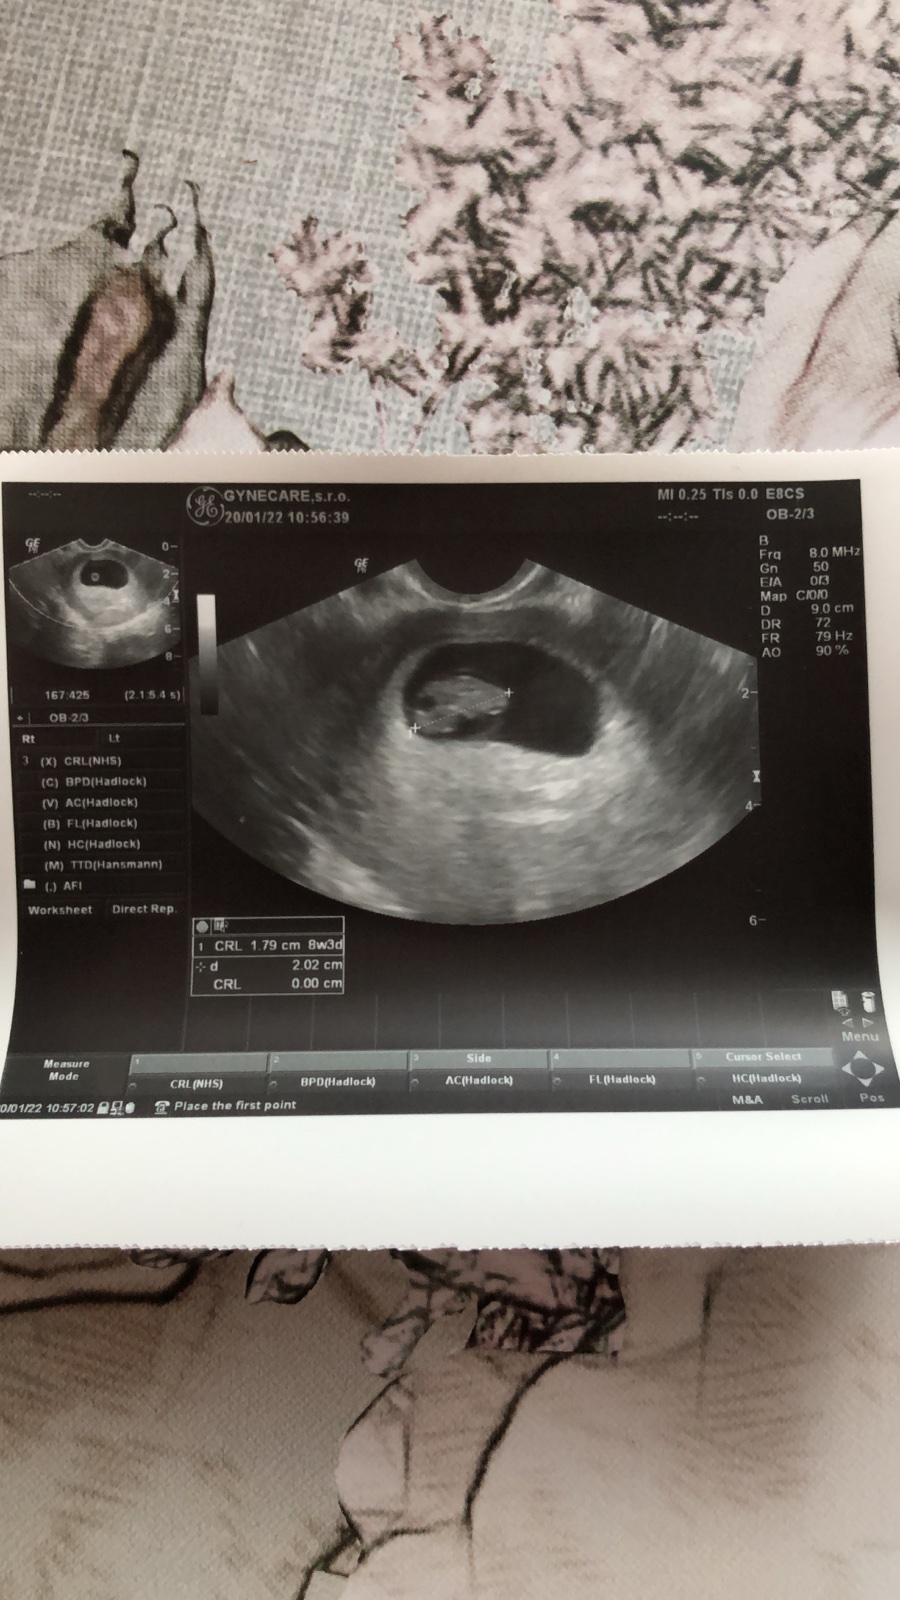

@lucia7933 ja keď som tiež videla test pozitívny tak už som sa nevedela dočkať toho dňa kedy pôjdem k doktorovi a v ten deň som mala take stresy keď som tam šla že či mimi bude zdravé a na všetko a keď som videla na tom ultrazvuku malú fazuľku zdravú tak som bola strašne štastna oplatilo sa počkať do toho 8tt lebo skôr by nič nevidel 🌸

Na prvom vyšetrení sme mali skoro 2cm❤️